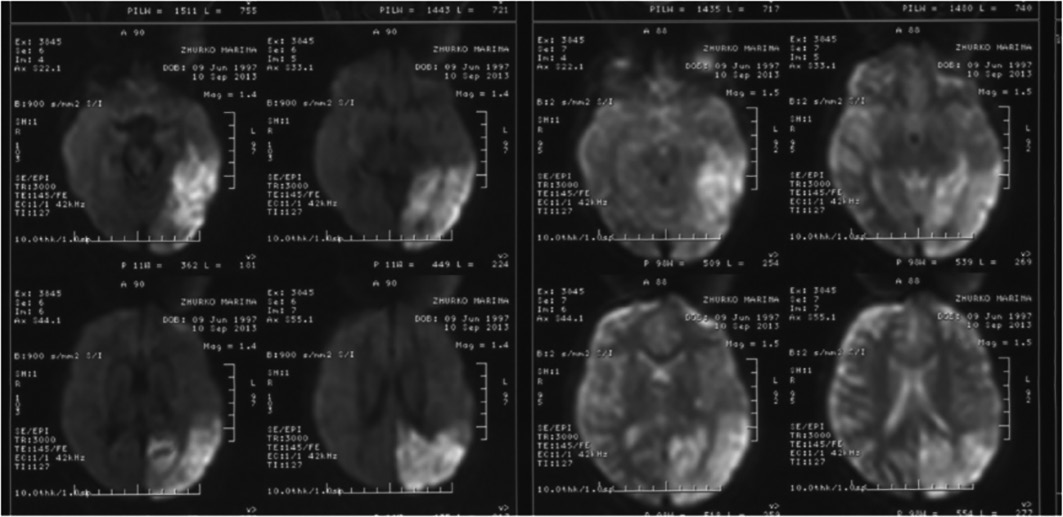

МРТ-сканирование острых ИПЭ при MELAS-синдроме обнаруживает нарушения в виде гиперинтенсивности сигнала в T2 и FLAIR, а также очаги «свежей» ишемии в режиме DWI (рис. 3). Повреждения не совпадают с бассейнами крупных мозговых артерий, но в значительной степени затрагивают кору и подлежащее белое вещество с умеренным поражением глубокого белого вещества. Острые повреждения мозга на МРТ при MELAS-синдроме могут изменяться, мигрировать или даже исчезать (характерна флуктуация очагов, определяемая при МРТ). Ангиография выявляет отсутствие выраженной сосудистой патологии: помимо нормальных результатов можно обнаружить увеличение калибра артерий, вен или капиллярную гиперемию.

Рис. 3. «Свежий» очаг ишемии в левой затылочно-височной доле у пациентки 14 лет.

MELAS-синдром в режиме DWI (собственное наблюдение авторов).